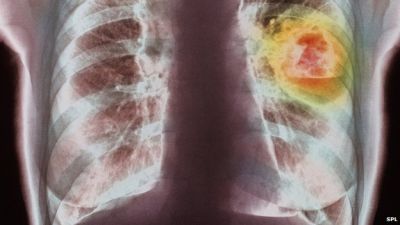

Lung cancer, mainly caused by smoking, was the most common cancer globally, accounting for about 13 percent of the total number, or 1.8 million cases.